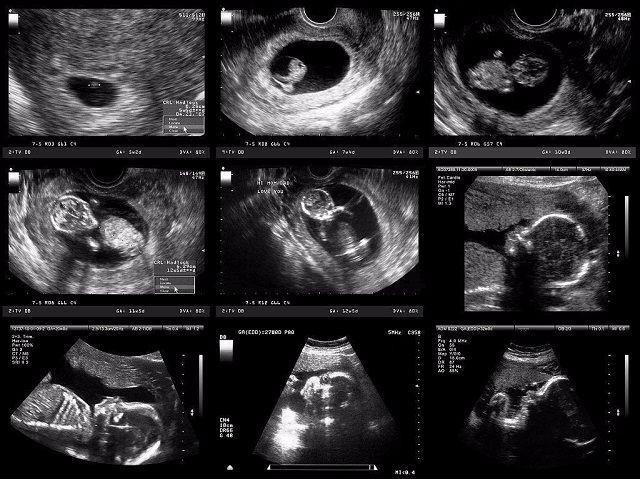

妈妈从孕育到孩子的出生,中间要经历10个月。网上有一组生动形象的动图,可以看出这十个月妈妈究竟经历了什么,这个期间,宝宝每个月在妈妈的肚子里的状态都是不一样的。如果有看过一个胎儿从开始孕育到出生10个月的不同形态,你就会感受到生命的神奇,宝宝在妈妈肚子里每个月不同的形态。

孕妈在刚刚怀孕的时候,宝宝那会儿还只是一个胚胎,被子宫包裹住也就只有鸡蛋那么大。如果孕妈反应激烈,呕吐恶心,这个时期的孕妈是非常难受的。

当宝宝在妈妈肚子里呆到第二个月的时候,胎儿从一个胚胎变成了雏形,而且孕妈的子宫壁也会越来越薄。